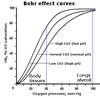

what is the structure of the substance carrying oxygen in the blood in RBCs

A RBC contains molecules of haemoglobin, made of 4 sub-units. Each sub-unit is a conjugated polypeptide chain in an alpha helix, i.e. GLOBIN (protein) + HAEM (prosthetic group)

There are 2 alpha chains and 2 beta chains.

Haem has the same structure as chlorophyll (porphyrin ring, iron in the centre)

what happens after the chloride shift in the lungs (3 marks)

At the lungs, hydrogen carbonate ions HCO3- re-enter RBCs and chloride ion Cl- leave the RBC to balance the charge.

HCO3- are reconverted to CO2 by the action of carbonic anhydrase.

CO2 DIFFUSES OUT + ENTERS THE ALVEOLI.